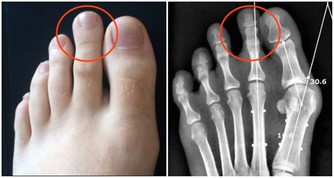

原因很簡單,因為卵巢那里長了不該長的東西,也就是腫瘤,這個東西是有體積的,隨著它迅速長大,要獲取生長空間,就會去擠壓周圍的器官,包括膀胱。你的膀胱總是被壓迫,讓它誤以為自己需要尿尿。